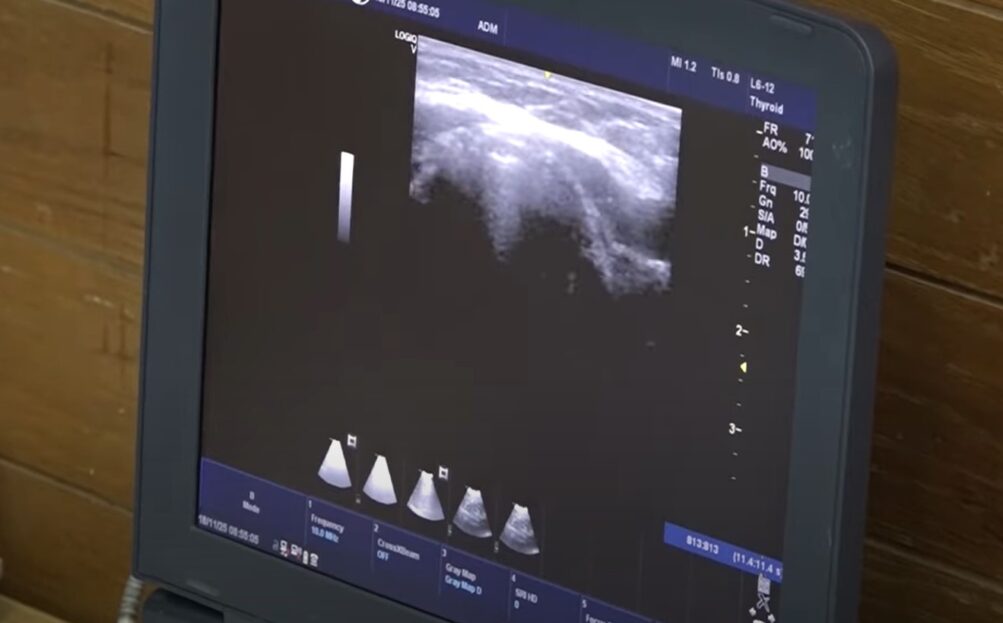

Dolovo je peto naseljeno mesto na teritoriji grada Pančeva u kojem su, u okviru zajedničkog projekta pančevačkog Doma zdravlja i rumunske opštine Božovići, organizovani besplatni preventivni pregledi. Kao i prethodnih nedelja, meštani su se odazvali pozivu u velikom broju. Kroz projekat „Jednakost u pružanju zdravstvenih usluga osetljivim grupama u Banatu“, građani širom Banata dobijaju mogućnost da brže i efikasnije obave najvažnije preglede, rekla je dr Zorica Sokić, direktorka Doma zdravlja.

– Dolovo je peto mesto gde se organizuju preventivni pregledi u sklopu IPA projekta prekogranične saradnje, naši partneri su i iz Rumunije, iz opštine Božovići. Ove aktivnosti su deo projekta kao preventivni pregledi i imamo kampanju gde treba da poradimo da sugrađani shvate koliko su preventivni pregledi važni. Ovaj projekat traje, ovo je prva godina i nastavljamo aktivnosti. Što se tiče opreme, a to su četiri automobila koji se uveliko koriste u terenskim službama, Službi patronaže i službi kućnog lečenja, kao i kombi vozilo za dijalizu, rekla je dr Sokić.